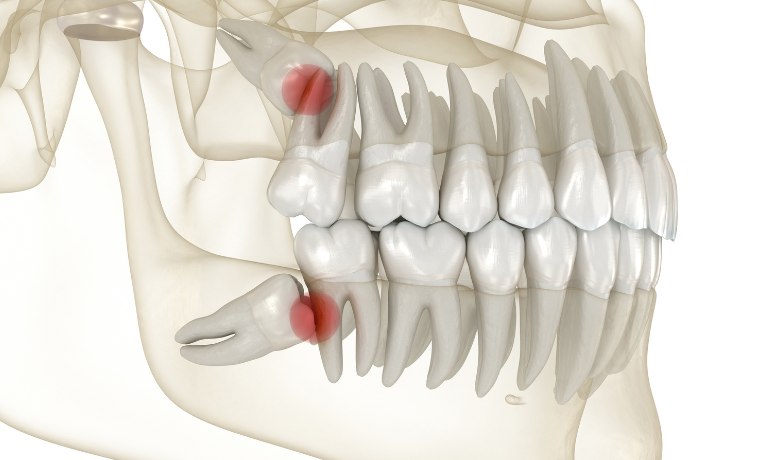

親知らずとは、一番奥に生えてくる永久歯のことで正式には「第三大臼歯」と呼ばれます。

奥歯の「6歳臼歯(第一大臼歯)」「12歳臼歯(第二大臼歯)」の、さらに奥に生えてきます。

現代人は食生活の変化などから顎の骨が小さくなる傾向があり、親知らずが最後に生えるための十分なスペースがないケースが増えています。

そのため、様々なトラブルを引き起こす原因となりやすいのです。

親知らずが横向きに生えてくると、手前の大切な歯(第二大臼歯)の根元を強く押し続け歯の根を溶かしてしまう(吸収)ことがあります。

3. 歯並びの悪化

親知らずが手前の歯を前方に押す力は、お口全体の歯並び(噛み合わせ)に影響を及ぼすことがあります。

特に矯正治療を終えた方や、これから治療を考える方にとって親知らずの存在は考慮すべき点となります。

特に下顎の親知らずの抜歯において、最も注意すべきなのは顎の骨の中を通る太い神経(下歯槽神経)や血管との位置関係です。

従来の二次元レントゲンでは、歯の根と神経が重なって写っているようにしか見えずその正確な距離や前後関係は「推測」するしかありませんでした。

当院では、歯科用CTを導入し骨の中の状態を「三次元の立体画像」で再構築します。これにより、以下のことが手術前に「目で見える」状態で把握できます。